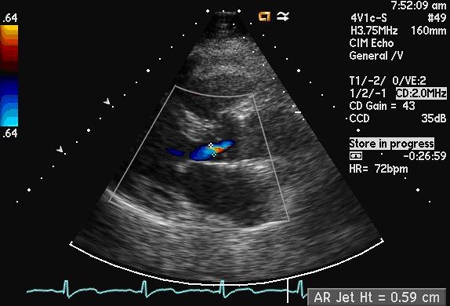

Dopplerfluxometria colorida

Exame

Uma das técnicas mais específicas e sensíveis usadas para julgar a gravidade do fluxo regurgitante, que usa a relação entre a largura do jato proximal e a via de saída do ventrículo esquerdo e a relação entre a área transversal do jato e a via de saída do ventrículo esquerdo. A vena contracta, que é a região mais estreita do jato regurgitante logo abaixo da valva aórtica, também pode ser usada.[24][Figure caption and citation for the preceding image starts]: Incidência do eixo paraesternal longitudinal demonstrando largura e altura de jato de regurgitação aórticaDos acervos Dr. Sanjeev Wasson e Dr. Nishant Kalra; usado com permissão [Citation ends].

[Figure caption and citation for the preceding image starts]: Incidência do eixo paraesternal longitudinal demonstrando o diâmetro da via de saída do ventrículo esquerdoDos acervos Dr. Sanjeev Wasson e Dr. Nishant Kalra; usado com permissão [Citation ends].

[Figure caption and citation for the preceding image starts]: Incidência do eixo paraesternal longitudinal mostrando vena contracta do jato de regurgitação aórticaDos acervos Dr. Sanjeev Wasson e Dr. Nishant Kalra; usado com permissão [Citation ends].

Antigamente era usado o comprimento da coluna de jato no ventrículo, mas esse critério atualmente não é mais considerado uma medida da gravidade.

Incidências paraesternais têm preferência sobre a incidência apical devido à melhor resolução axial.

Resultado

detecção e quantificação do fluxo regurgitante